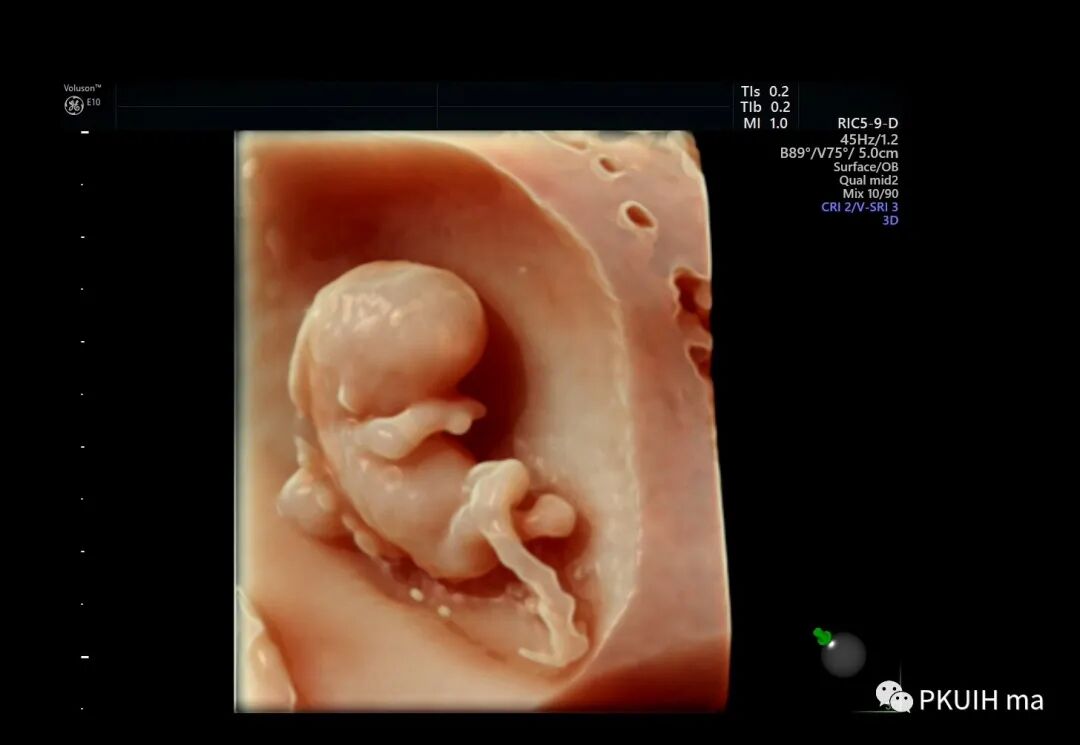

早孕三维

早孕双绒双羊双胎三维